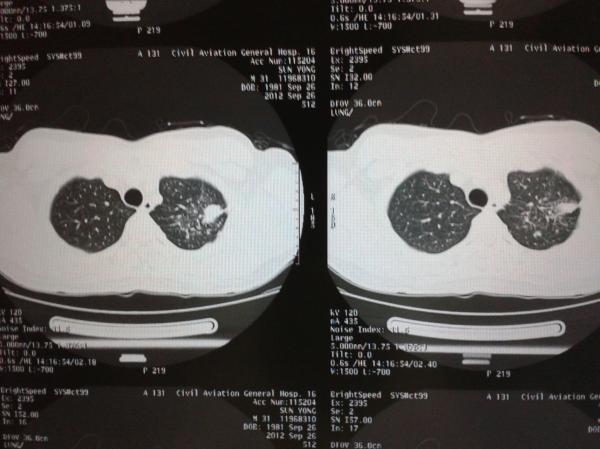

½ñÈÕÌå¼ì£¬ÐØÆ¬ÏÔʾ×óÐØÓÐÒõÓ°£¬ºóÀ´×öÁËct£¬ÄÄλ³æÓÒÄܰï×Å·ÖÎöÏÂ

¹â¿´Õâ¸ö»¹²»ÐУ¬Òª¸¨Öú¼ì²é£¬¿ÉÄÜÊÇŧÖס¢½áºË¡¢°©¡¢·ÎÑס¢³¾·Î¡¢»ú»¯ñ£ºÛµÈµÈµÈµÈ

²¡ÔîλÓÚ×ó·Î¼â¶Î£¬ÖÜΧÓÐÎÀÐÇÔÊ×ÏÈ¿¼ÂÇΪ½áºËÇò£¬Çë½áºÏÁÙ´²ÁÙ´²»¯Ñé¼ì²é¼°ÌåÕ÷¡£

½áºÏÖ¢×´£¬Åųý½áºËºÍÖ×Áö£¬Ò»¶¨Òª½áºÏÖ¢×´À´£¬ÄêÁ䣬ְҵ£¬ÎüÑÌÊ·µÈµÈÀ´¼ÓÒÔÅжϡ£

ÈôÊÇÄêÇáÈË¿¼ÂǽáºË¶àһЩ£¬±Ï¾¹Ôڷμⲿ¡£½¨Òé×ö¸öPPD¼°¶¨ÆÚ¸´²é